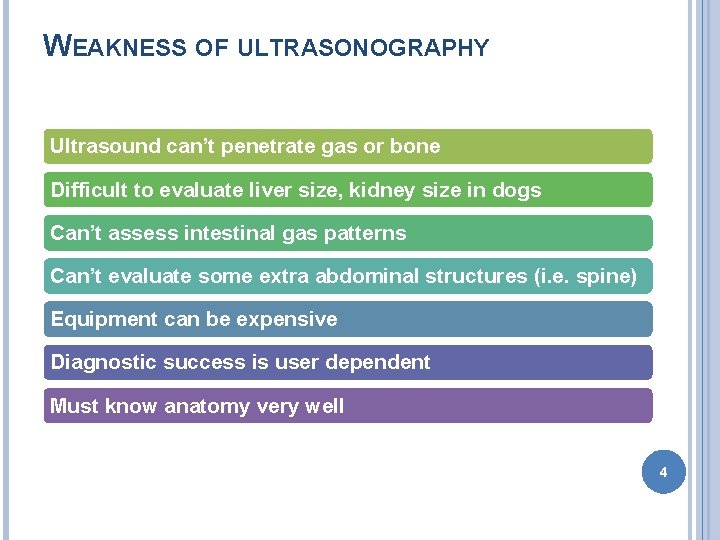

WEAKNESS OF ULTRASONOGRAPHY Ultrasound can’t penetrate gas or bone Difficult to evaluate liver size, kidney size in dogs Can’t assess intestinal gas patterns Can’t evaluate some extra abdominal structures (i. e. spine) Equipment can be expensive Diagnostic success is user dependent Must know anatomy very well 4